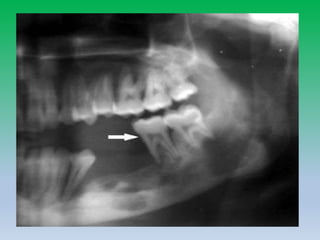

• 42-year-old woman

with periapicalcyst.

• Cropped panoramic

radiograph shows

radiolucent

lesion(arrowhead) in

posterior body of

ramus of mandible

with displacement of

mandibular canal

(arrow).